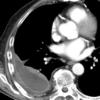

huge effusion CT